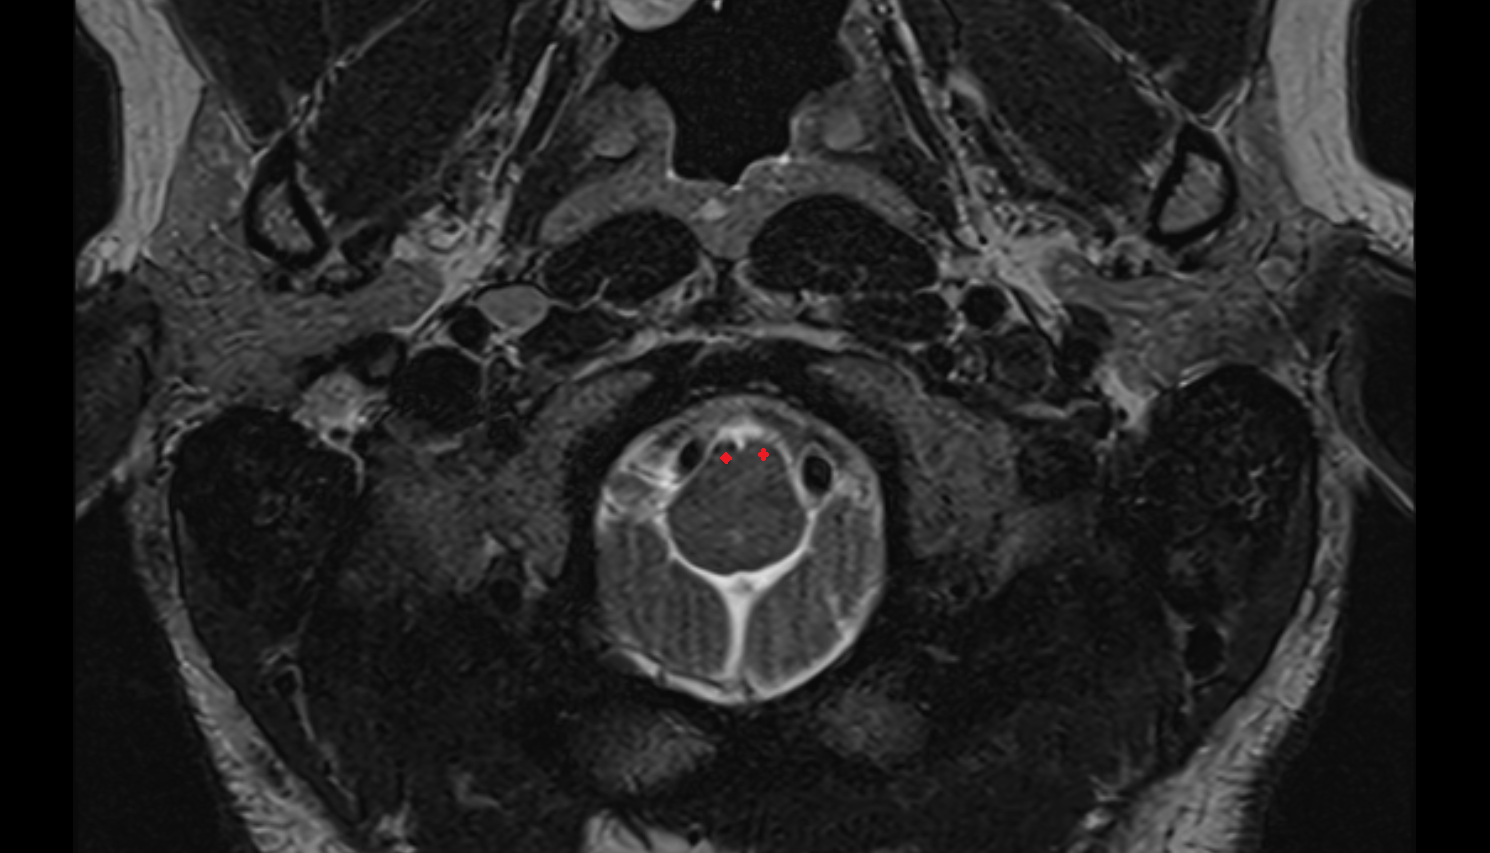

- Upper cervical spinal cord

- Spinal cord

- subarachnoid space of spinal cord